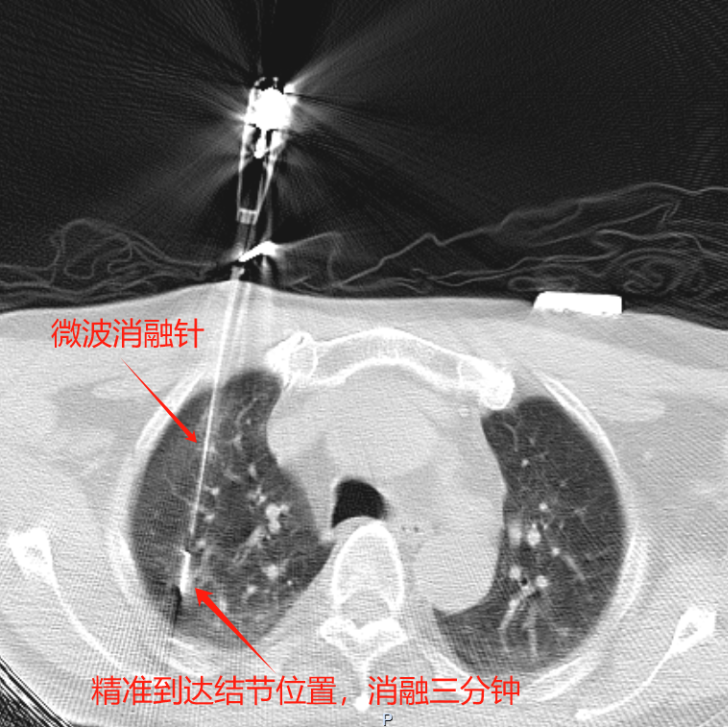

消融中,消融针精准到达结节部位

手术由我院呼吸与危重症医学科学科带头人廖江荣教授主刀,3分钟便完成了肺结节的微波消融,术后3天钱大爷顺利出院。